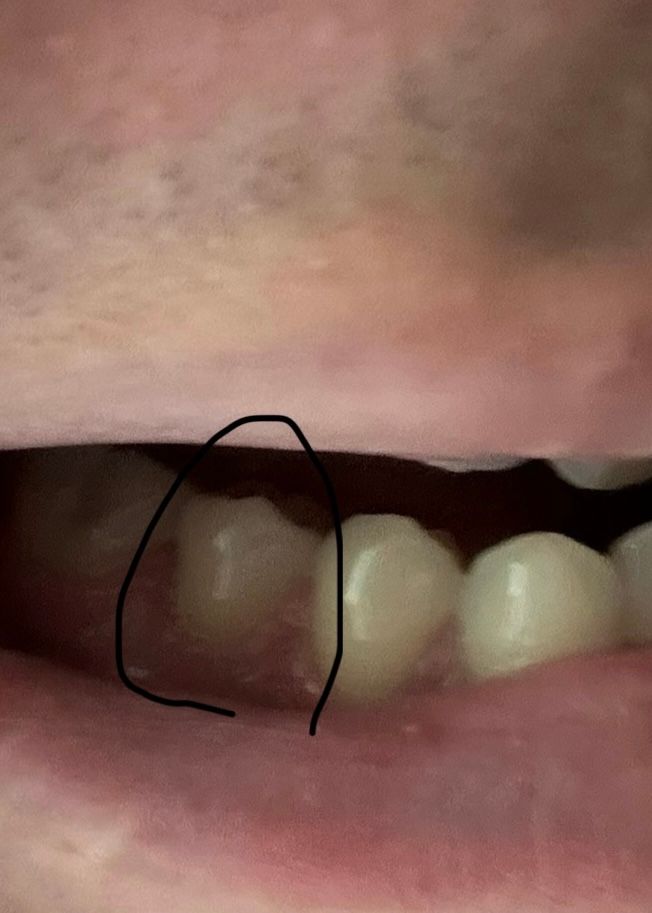

치아 퇴축인지 알고싶습니다 심한편인지

제목 그대로 밑 어금니 쪽에 동그라미 친 부분 포함아닌 치아쪽 잇몸 퇴축이 맞는지 심한폄인지 알고싶습니다 점점 잇몸이 내려가는거 같아서 질문 남깁니다 양치를 쫌 오래하는 편이긴합니다

사진으로는 크게 잇몸이 퇴축되어있는 것으로는 보이지 않고 마모는 조금 되어 있는 것 같습니다.

현재 사진으로는 정확히 판단하기 어려우나 잇몸과 치아 경계 부위가 마모된 것으로 보여지기는 합니다. 이는 치아의 퇴축과 더불어 치아의 마모가 같이 나타났을 가능성이 매우 높아 보입니다.

올려주신 임상사진 만으로 정확한 평가는 불가능하나, 잇몸퇴축이 심해 보이지는 않습니다.

저정도면 잇몸이 크게 퇴축된상태는 아니니 너무 걱정은 안하셔도 될것같습니다. 양치를 너무 자주 하거나 강하게 하는것만 조심해주세요.

사진상으로 봤을때 잇몸퇴축이 심하진 않습니다 양치질을 길게 하는 것은 큰 상관은 없습니다 다만 가로로 슥슥 밀면서 하는 것은 삼가시기 바랍니다